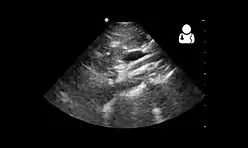

Diagnosis is can be difficult, and usually one of exclusion. SMA syndrome is generally considered only after people have undergone an extensive evaluation of their gastrointestinal tract including upper endoscopy, and evaluation for various malabsorptive, ulcerative and inflammatory instestinal conditions with a higher diagnostic frequency. Diagnosis may follow X-ray examination revealing duodenal dilation followed by abrupt constriction proximal to the overlying SMA, as well as a delay in transit of four to six hours through the gastroduodenal region. Standard diagnostic exams include abdominal and pelvic computed tomography (CT) scan with oral and IV contrast, upper gastrointestinal series (UGI), and, for equivocal cases, hypotonic duodenography. In addition, vascular imaging studies such as ultrasound and contrast angiography may be used to indicate increased bloodflow velocity through the SMA or a narrowed SMA angle.[13][14]

Upper gastrointestinal series showing extreme duodenal dilation (white arrow) abruptly preceding constriction by the SMA.- Ultrasound showing SMA syndrome[19]

Ultrasound showing SMA syndrome[19]